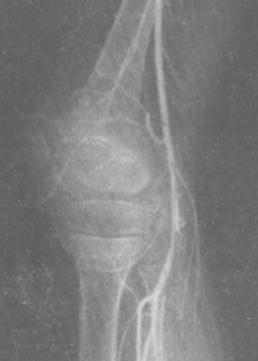

Рис. 8.46. Ангиоартрограмма

· Диагностику поражений околосуставных тканей проводят с помощью ангиоартрографии или регионарной артериографии. Данный метод применяют также при подозрении на суставную опухоль. Ангиографию осуществляют через открытый периферический сосуд. Серия рентгенограмм состоит из ~10 снимков, а общая продолжительность съемки составляет 40 секунд (фиксируют все фазы кровотока исследуемой области). Рентгенографию коленного сустава выполняют в боковой проекции. · Для оценки суставов позвоночника применяют компьютерную томографию, которая позволяет различать невидимые изменения мягкотканных и костных структур. Сканирование проводят в краниальном направлении срезами толщиной 2-5 мм. Одновременно изучают 1-2 сегмента в соответствии с рентгенологическими данными. Для обследования одного сегмента выполняют 6-12 срезов в зависимости от их толщины.